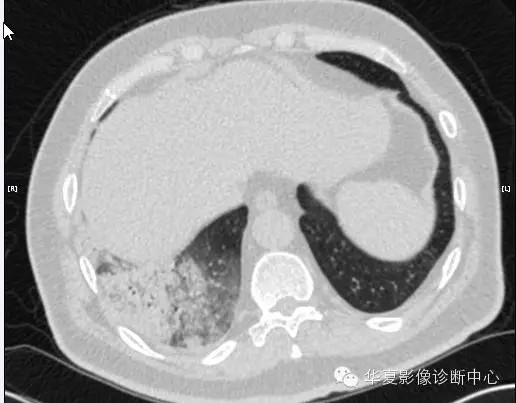

【病例学习】甲型H7N9禽流感一例

男性 63

发热咳嗽5天

2013-4-5拍片示右肺实变,收入院,追问病史,发病期间肌肉酸痛,头痛,无腹痛腹泻,无明显胸闷气急,无意识改变。有高血压病史,无其它病史。

2013-4-7CT进一步检查。

最终诊断:H7N9。